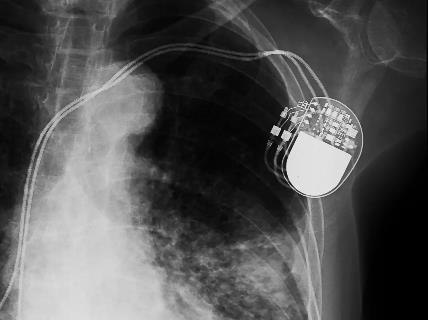

Xray picture of a pacemaker. Battery occupies more than half of the total volume

Active Implantable Medical Devices (AIMDs) are electronic devices typically powered by non-rechargeable batteries. To ensure longterm operation, the battery must store sufficient energy, which often results in a bulky form factor, frequently occupying more than half of the total device volume, as illustrated by the X-ray image. Once the battery is depleted, surgical replacement of the entire device remains the only option. In some cases, the original device cannot be explanted, requiring a new device to be implanted alongside it. This leads to a poor patient experience, long-term biocompatibility challenges, and increased costs associated with repeated surgeries and device replacements. Furthermore, device longevity varies significantly between patients, depending on usage patterns and implantation quality.